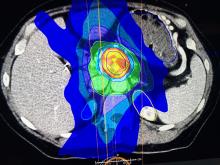

PET-CT | December 04, 2020

This is an example of Canon's Advanced intelligent Clear-IQ Engine (AiCE) AI-driven image reconstruction software that is now being used to improve image quality on the Canon Celesteion Prime PET/CT nuclear imaging system. The deep learning is used to enhance the iterative reconstruction used to reduce noise and sharped high contrast resolution on positron emission tomography (PET) images from the digital PET detector used on the system.

This example is a whole-body FGD PET scan of a patient with a large BMI with lung cancer.

The Cartesion Prime PET/CT is the industry’s only air-cooled digital PET/CT, provides variable bed time (vBT) acquisition as a standard feature. This and the new FDA 510(k)-pending AiCE technology were highlighted at the 2020 Radiological Society of North America (RSNA) virtual meeting.